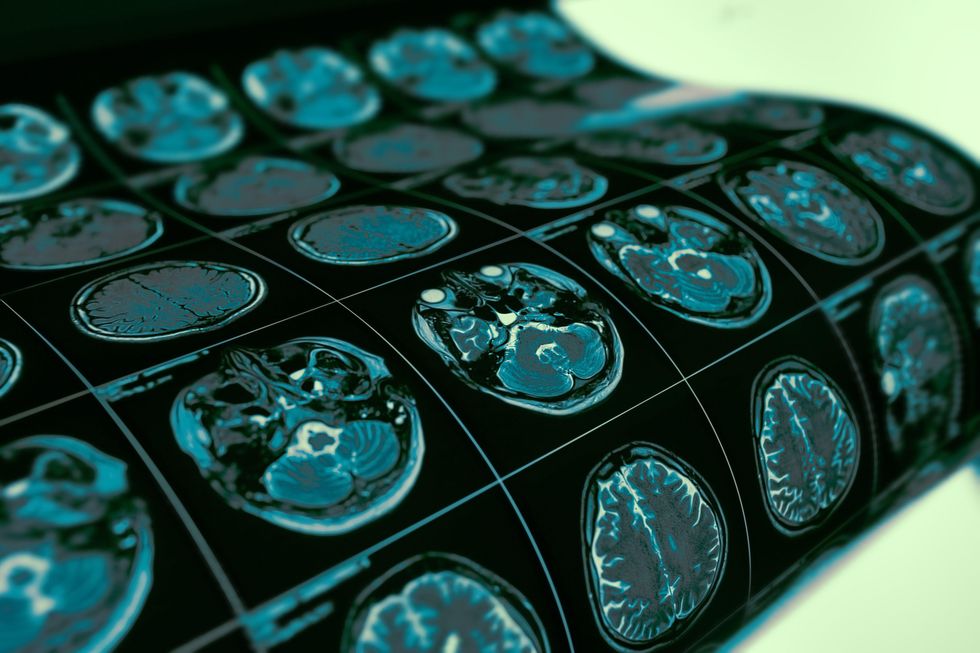

A doctor who was diagnosed with incurable brain cancer remains disease-free after a year following experimental treatment (Yuriy Klochan/Alamy)

On Monday, he wrote on X to say he had an MRI scan last week and there was still no sign of recurrence.